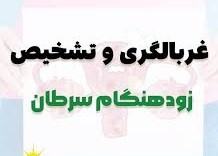

فیلم آموزشی/هفته پویش ملی مبارزه با سرطان

غربالگری و تشخیص زود هنگام نجات بخش زندگی

دکتر منصور روزدار/سرپرست هیات پزشکی ورزشی استان خوزستان